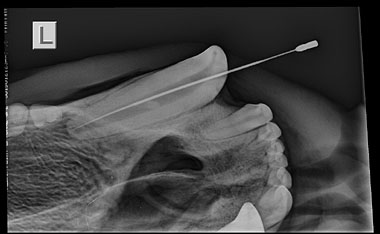

Arktos HWP Left Upper Canine Pulp Cavity

The Vita was set up ‘bear-side’ to allow a number of radiographs to be taken throughout the procedure, with near instant imaging allowing quick diagnosis and treatment planning to be decided.

The X-rays quickly revealed that Arktos would require a root canal procedure, rather than extraction as initially thought, by veterinary dental expert Norman Johnston, who was carrying out the treatment.